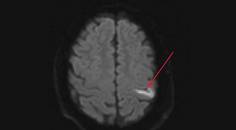

Stroke Snapshot: Intracranial MRI Vessel-Wall Imaging

Mitchell Barnes, DO; Parham Moftakhar, MDMitchell Barnes, DO; Parham Moftakhar, MD